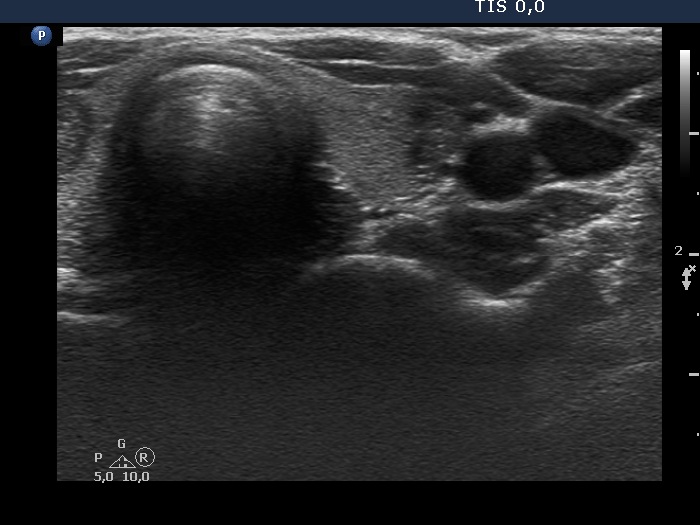

First examination (first row of images)

Clinical data: A 21-year-old woman was referred for evaluation on a nodular goiter. She has noticed an enlargement in the left lobe for a year. On evaluation in another institute, a cystic nodule was diagnosed with a 26 mm maximal diameter and 3 mL brown fluid was aspirated. Cytology resulted in benign cystic lesion.

Palpation: The right lobe was suspicious having a nodule.

Laboratory test: TSH 2.21 mIU/L.

Ultrasonography. The thyroid was echonormal and presented a moderately hypoechoic nodule in the right lobe and a cystic nodule with minimally hypoechoic solid part corresponding to the previously aspirated cystic lesion. The largest diameter of the latter was 11 mm which means that cyst has not refilled. The nodule in the right lobe showed irregular, more hypoechoic areas all along at the periphery. This pattern mimicked halo sign, but indeed the lesion did not have a real halo. The vascularization of the nodule in the right lobe presented an irregularly increased intranodular blood flow while the lesion in the left lobe did signs of perinodular vascularization.

Cytology was performed form the lesion in the right lobe and resulted in follicular proliferation.

Combined ultrasound-cytological diagnosis was benign follicular proliferation.

Suggestion: ultrasound in a year.